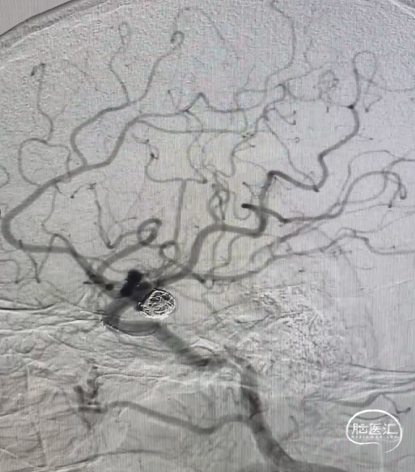

术后造影显示各分支血管通畅,动脉瘤不再显影。

术后影像及随访

患者术后恢复良好,术后4天出院,出院mRS 0分。

术后3个月门诊随访,复查头颈部CTA:动脉瘤不显影,载瘤动脉通畅。

复查CTP未见明显异常。